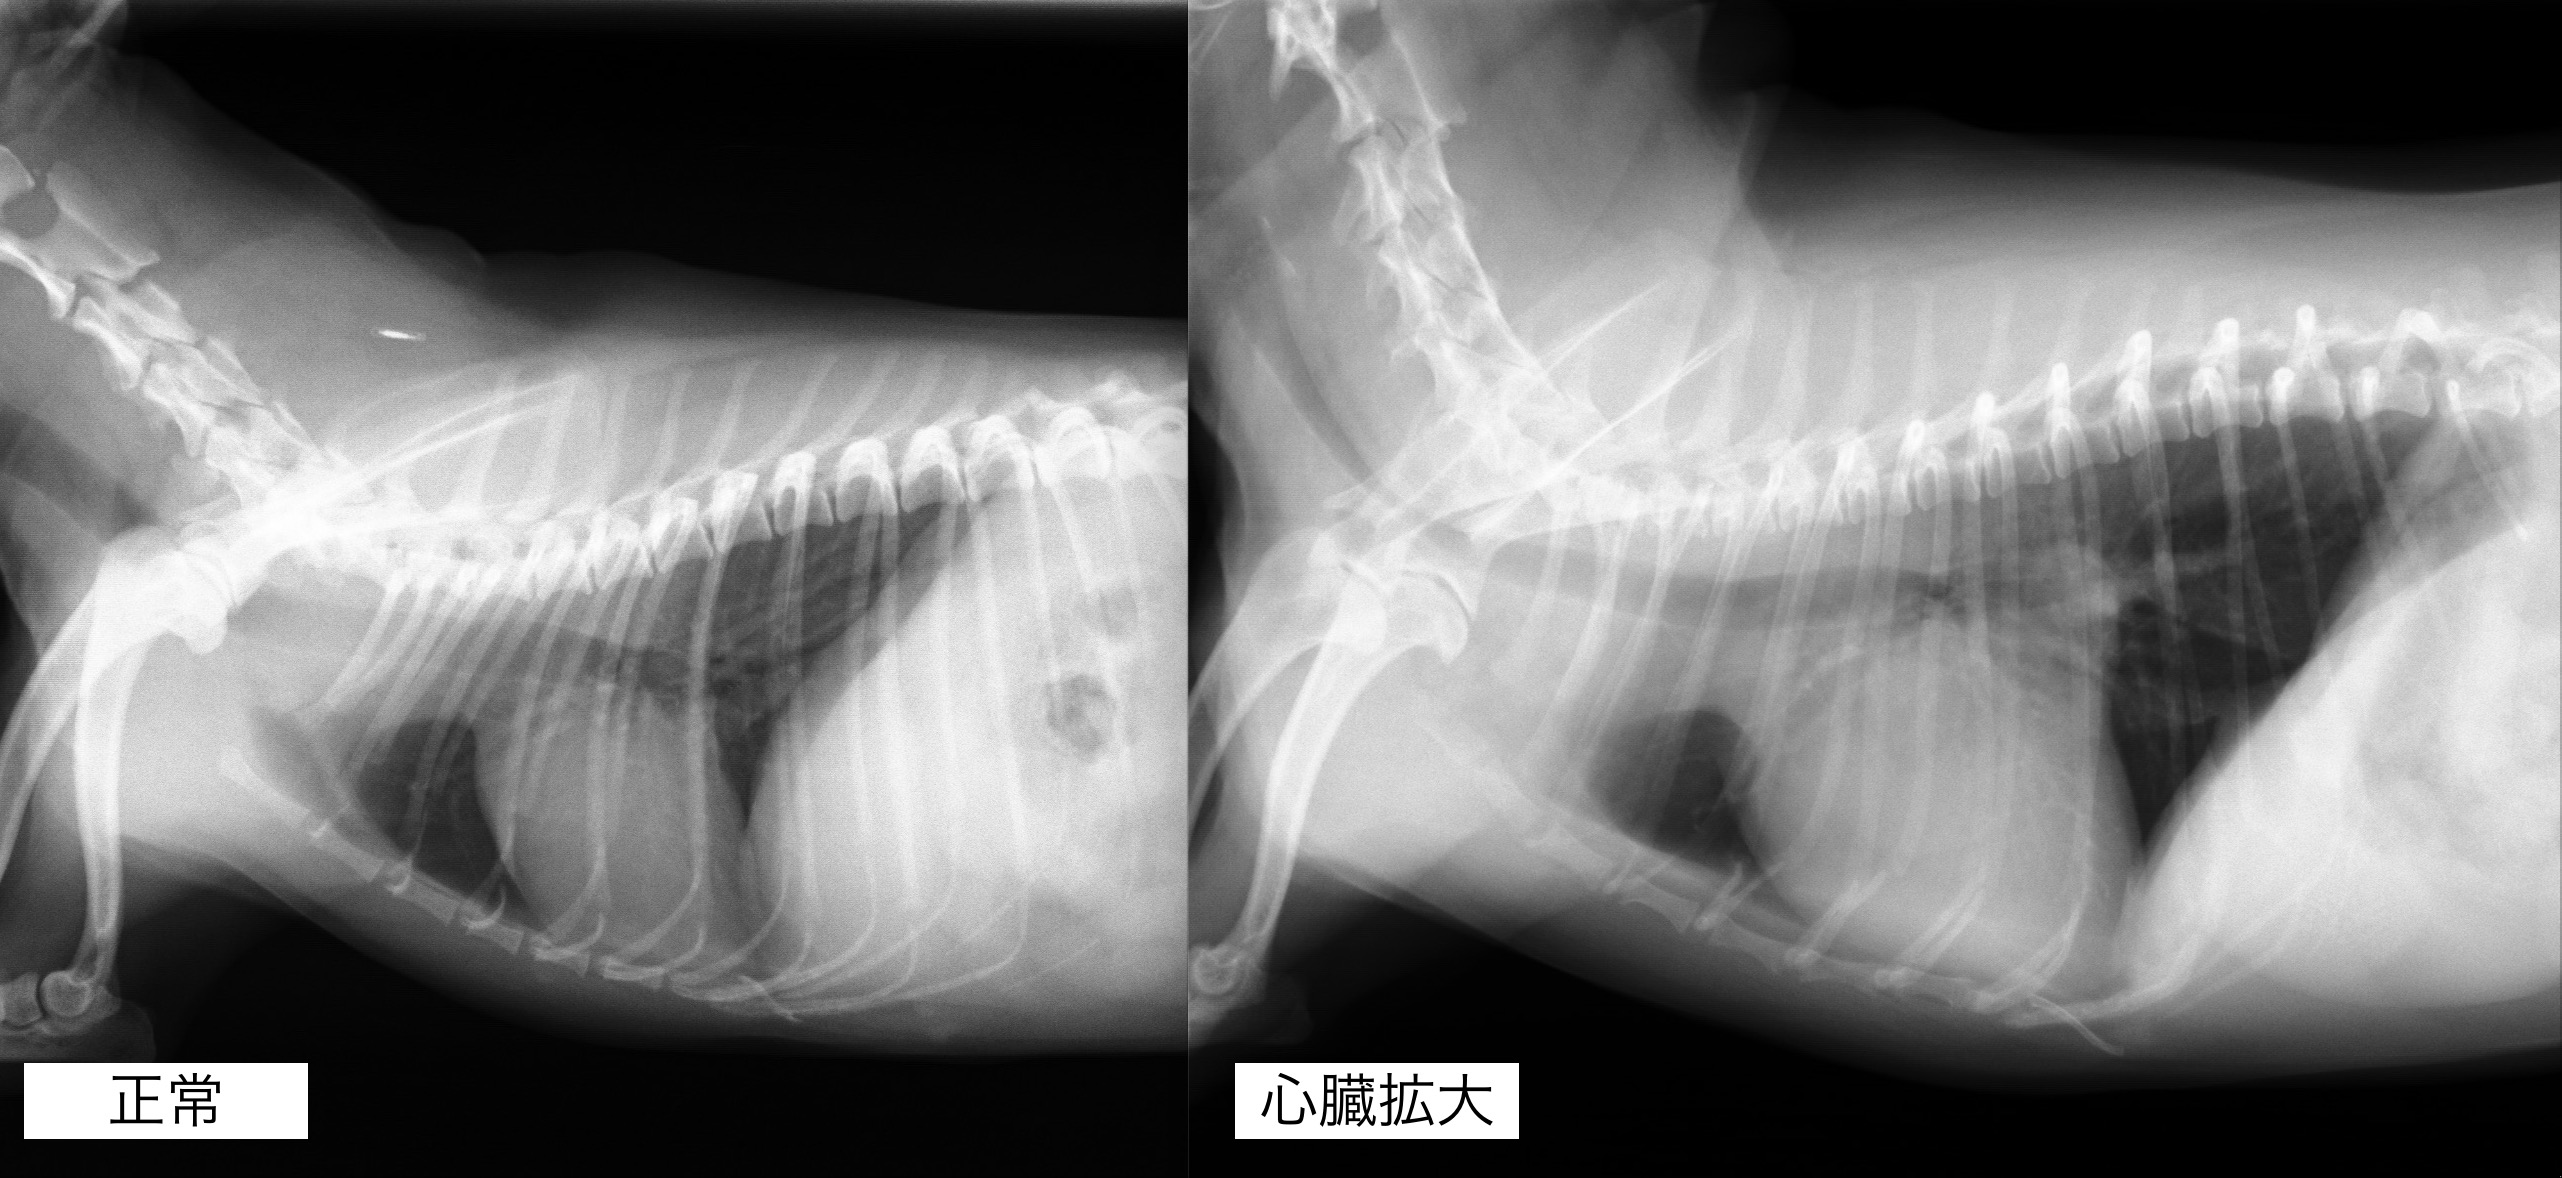

聴診検査にて心雑音が観察され、レントゲンん検査では心臓の明らかな拡大が認められました。

心臓の拡大はやや改善しており、咳の頻度も減っているとのことでした。